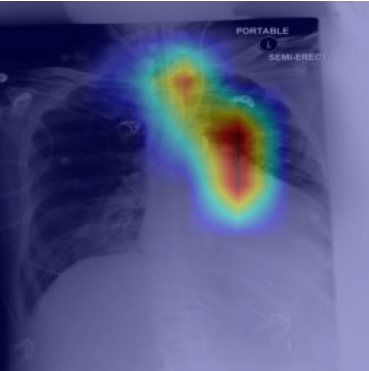

5.2 Visualization of attention weights

Fig. 5 presents a qualitative visualization of the learned word-to-region correspondences facilitated by our AGA framework. The top row shows the original medical images, including both chest X-rays (CXR) and endoscopic ultrasound (EUS) images. The bottom row displays the corresponding heatmaps generated by our model, where warmer colors denote higher activation weights, indicating stronger associations between specific image regions and the given medical concepts. For Atelectasis and Pneumonia, the model focuses on appropriate pulmonary regions, demonstrating strong localization aligned with radiological pathology. For the SMTs domain, terms like low-echoic mass and protruded into the cavity activate precisely the relevant interior structures of the lesion in EUS images. The distinct and interpretable activation patterns validate the effectiveness of our AGA mechanism in achieving fine-grained multimodal alignment.

Atelectasis

Pneumonia